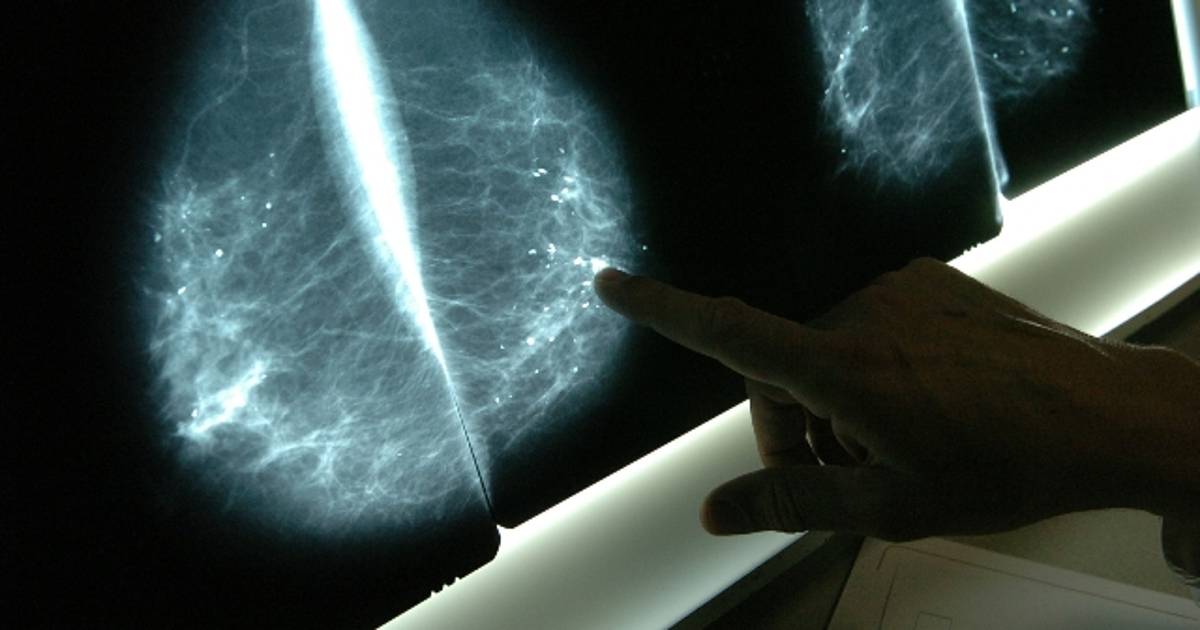

Volver menos tortuosas estas radiografías permitirá salvar más vidas en un futuro

EU - Mujeres que se han tomado una mamografía con anterioridad, conocerán muchas veces el cansancio y el dolor que involucra, en ocasiones, tomarse el examen.

Este percance, evidenciado por una investigación de la fundación Kadence International, es una de las razones principales por las que una mujer rechaza hacérselo y detectar a tiempo el cáncer de seno.

El proceso involucra tomar una placa de rayos X al comprimir los senos entre dos superficies planas. Por esto, la manufacturera Hologic anunció una invitación a cambiar este procedimiento para siempre.